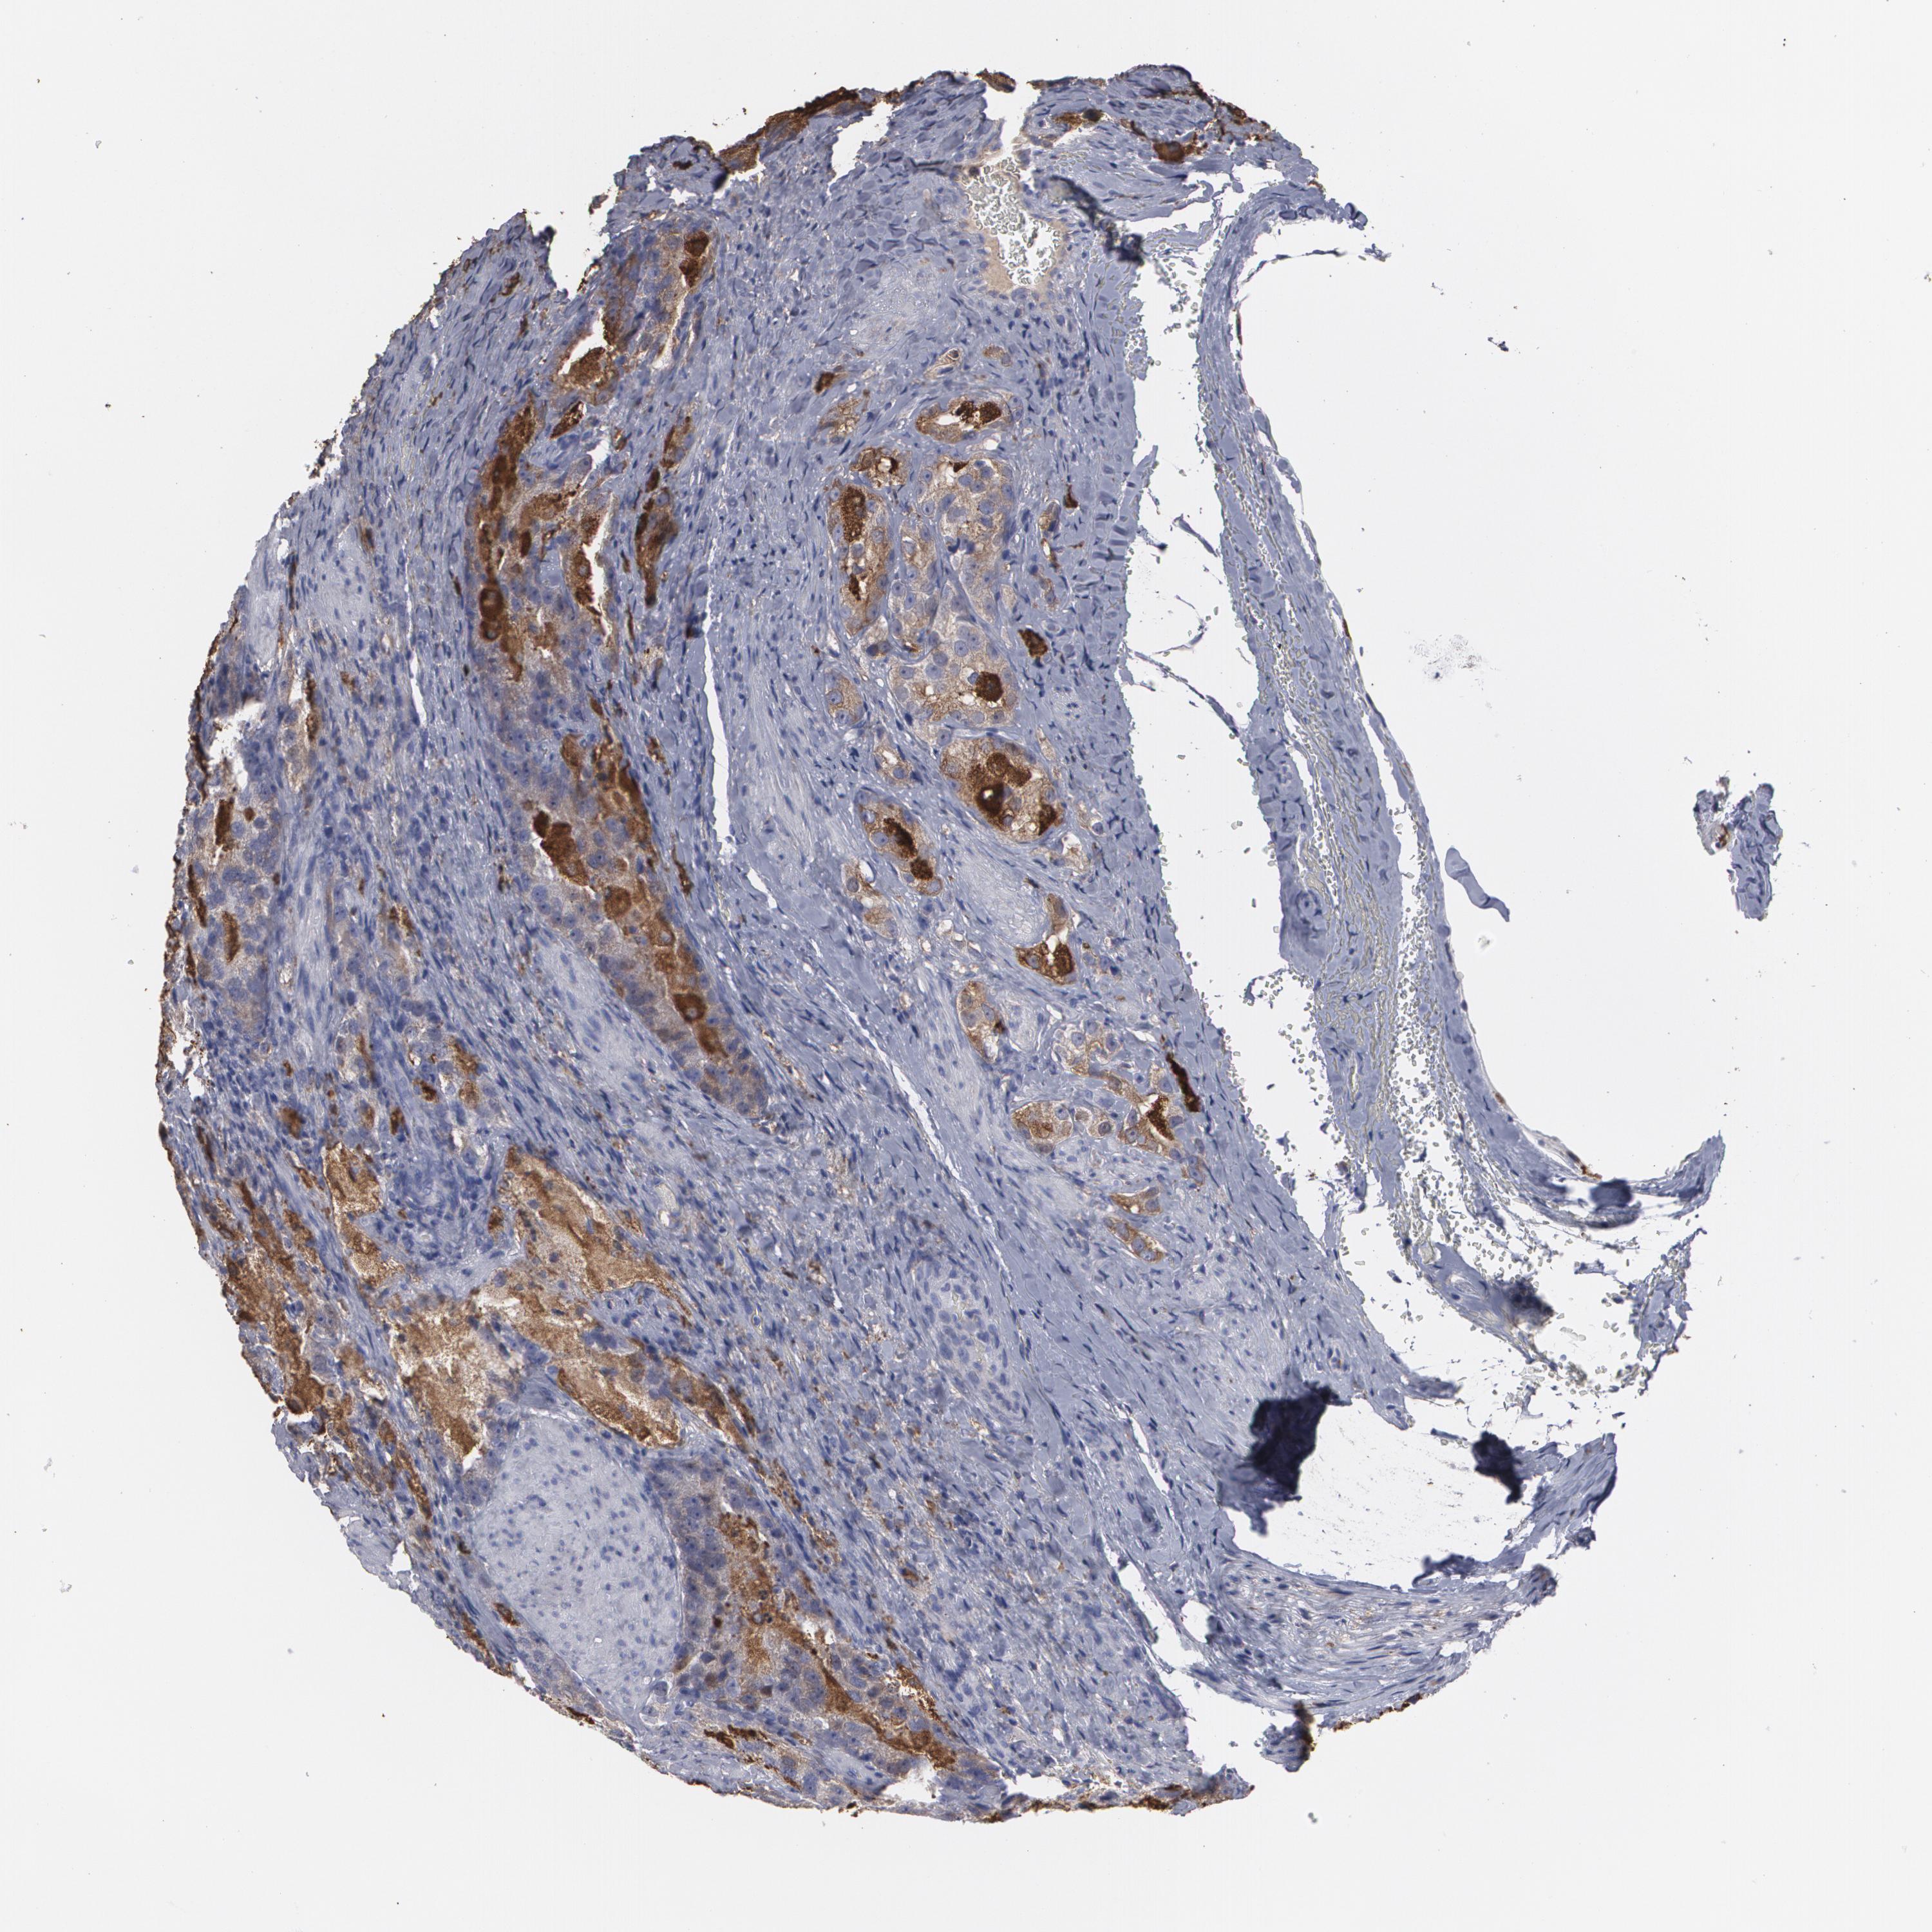

PROSTATE CANCER - Protein expressioni

A mouse-over function shows sample information and annotation data. Click on an image to view it in a full screen mode. Samples can be filtered based on level of antibody staining by selecting one or several of the following categories: high, medium, low and not detected. The assay and annotation is described here.

Antibody stainingi

Antibody staining in the annotated cell types in the current human tissue is reported as not detected, low, medium, or high, based on conventional immunohistochemistry profiling in selected tissues. This score is based on the combination of the staining intensity and fraction of stained cells.

Each image is clickable and will lead to virtual microscopy that enables deeper exploration of all samples and also displays staining intensity scores, fraction scores and subcellular localization as well as patient and tissue information for each sample.

Antibody HPA001536

Antibody CAB035996

Staining

High

Medium

Low

Not detected

Intensity

Strong

Moderate

Weak

Negative

Quantity

>75%

75%-25%

<25%

None

Location

Nuclear

Cytoplasmic/membranous

Cytoplasmic/membranous,nuclear

Adenocarcinoma, Medium grade

Adenocarcinoma, High grade

Adenocarcinoma, Low grade